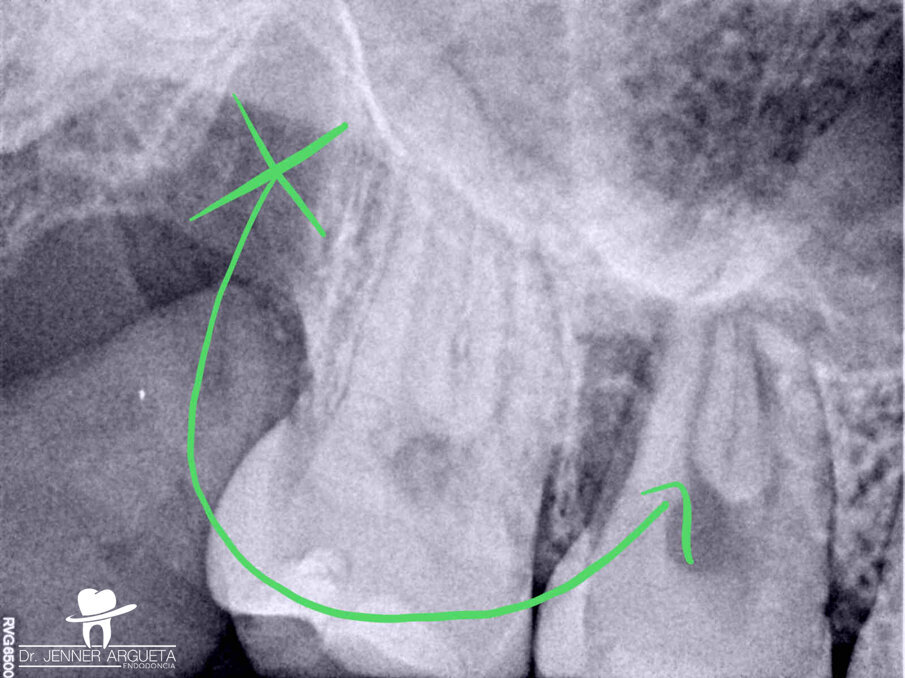

The patient showed up to the clinic eight months later with signs and symptoms of pulp necrosis and acute periapical abscess; a periapical radiolucency was present, and the retromolar area was healed (Fig. 6). In cases like this, where the coronal structure remains intact, it is advisable to take a conservative approach to the root canal therapy, using new technology available in endodontics to achieve good results. The endodontic access opening was created using high-speed burs and ultrasonic tips. The cleaning and shaping protocol was performed with flexible needles and controlled memory files (Aurum Blue, Meta Biomed), especially important properties for entry to the root canals through the conservative access (Figs. 7a & b).

Fig. 6:

Eight-month post-op radiograph. The retromolar area had healed, but the transplanted tooth showed signs of pulp necrosis and periapical disease.